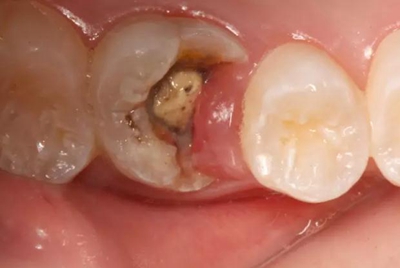

病例一 女性,20歲,大學生,要求補牙,檢查口內(nèi)可見A6大面積缺損,近中牙齦息肉,拍X片,根管充填物略差,但根周未見明顯陰影,口內(nèi)檢查無叩痛。建議患者冠延長手術+高嵌體修復。

患牙遠中邊緣嵴完整,強度沒有降低,故擬保留遠中邊緣嵴,高嵌體修復。首先去除腐質(zhì)及原墊底材料,流體樹脂+3M Z350XT樹脂墊底。局麻下行冠延長手術。在此需要提及個人的一個觀點。冠延長手術原則上要求3-6個月以上才能永久修復。但是個人喜歡后牙肩臺建立在齦上,所以修復后的修復體邊緣位于牙齦上方1mm,對牙周的愈合影響較?。ㄈ绻麨辇l下邊緣則要慎重),故該患者術中按照齦上邊緣的設計進行冠延長手術。以下為術中: